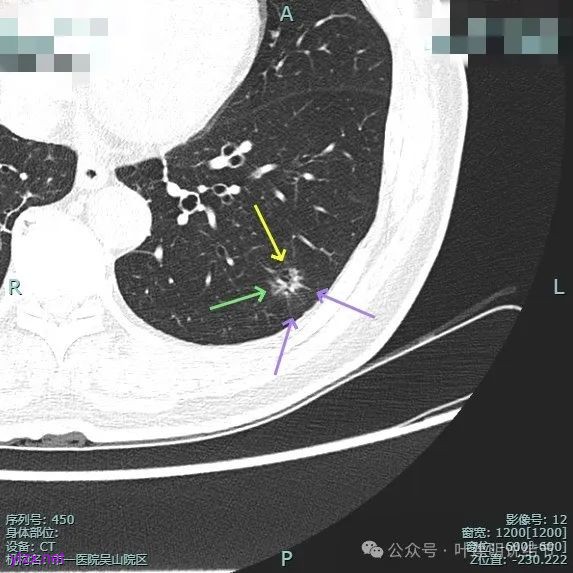

病灶毛刺空泡(或细支气管扩张)都有,表面不平,灶内杂乱。

但纵向看是偏条状些的,密度较高,边上有少许磨玻璃成分,磨玻璃部分略显模糊。

中间实性部分密度过高,边上的的毛刺显得过长,且不太锐利。

实性成分密度较高,边上有淡磨玻璃成分,毛刺明显。

密度高,边上磨玻璃成分淡,表面不平,毛刺不太锐利,整体感觉缺乏收缩力。

相应支气管有扩张,边上的磨玻璃成分偏糊,界限欠清。

进入的血管没有异常增粗,棘突不太锐利,磨玻璃成分偏糊。

上图倒是血管显得有点异常增粗的,总体膨胀性不强,收缩力不够。

我的意见是纵向看线状,考虑慢性炎伴纤维增生可能性大些,建议4-6个月复查。